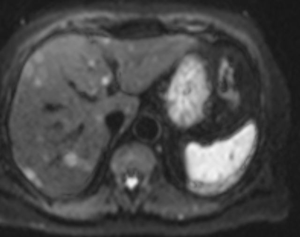

МР-диагностика образований печени (с использованием гепатоспецифичного контрастного препарата)